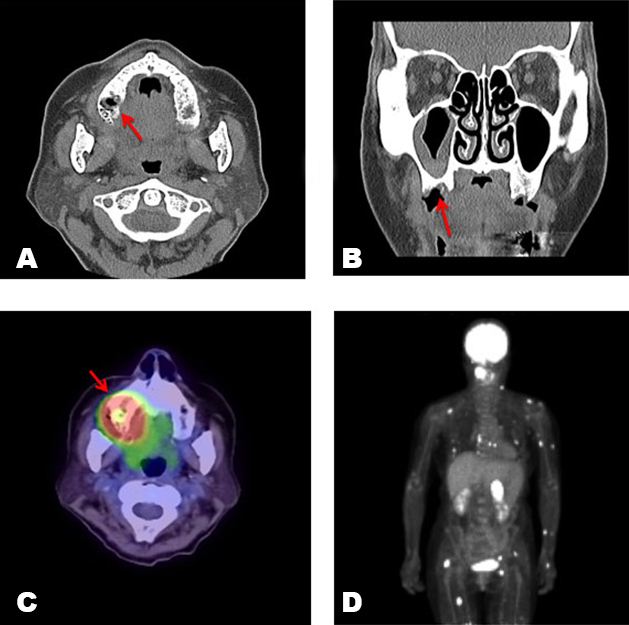

A 61-year-old woman was treated with extraction of the maxillary right first and second molars at dental clinic in August 2017. One month later, the patient was referred to Department of Dentistry and Oral Surgery, because of delayed socket healing after dental extraction. Her past medical history was significant for RA and myocardial infarction. The RA had been treated with MTX 12 mg once weekly since 2011. She had been taking cilostazol for the previous episode of myocardial infarction. There was no history of the use of other antirheumatic drugs, corticosteroids, antiresorptive, and antiangiogenic medications. At the first visit, oral examination revealed a 15 mm × 15 mm area of exposed bone with necrotic soft tissue in the right posterior maxilla (Figure 1). A reddish swelling of the gingiva was found in the surrounding exposed bone, but there was no bleeding or pain. A dental panoramic radiograph revealed absence of healing of the extraction sockets and osteosclerosis around the right upper molar. Computed tomography (CT) showed thickening of the maxillary sinus mucosa, while there was no obvious separation of the sequestrum (Figure 2A and Figure 2B). Abnormal fluorodeoxyglucose uptake (maximum standardized uptake value, 13.8) in the right posterior maxilla area was observed on positron emission tomography/CT (PET/CT) (Figure 2C). Furthermore, uptake by other organs, including the adrenal gland, multiple intrapulmonary nodules, muscles, bones, and lymph nodes was observed (Figure 2D). Blood tests revealed elevated levels of C-reactive protein (CRP, 2.01 mg/dL), soluble interleukin-2 receptor (sIL-2R, 1980 U/μL), and lactate dehydrogenase (LDH, 431 U/L), respectively. We considered the possibility of MTX-LPD and other malignant tumors, and performed an incisional biopsy in the exposed bone and surrounding mucosal tissue. Histopathological findings of the bone confirmed a sequestrum with empty osteocytic lacunae and bacterial infection, including colonies of Actinomyces spp. in the marrow space. It did not reveal tumor cells, including atypical lymphocytes, usually found in MTXL-PD. Pathological analysis of the mucosal tissue showed infiltration of numerous lymphocytes and diffuse proliferation of large-sized atypical lymphoid cells under the epithelium surrounding the gingiva (Figure 3A). Immunohistochemical analysis showed CD20+, CD3−,CD5−, and CD10− cells. Ki67+ was detected in 80% of these cells. Additionally, Epstein–Barr encoding region (EBER) was detected in almost all atypical cells by in situ hybridization (Figure 3B). Based on these findings, the histopathological diagnosis was diffuse large B-cell lymphoma (DLBCL) with jaw osteonecrosis. Therefore, we referred the patient to the Department of Hematology in our hospital. She was diagnosed with MTX-LPD based on the history of MTX therapy for RA, and MTX was discontinued immediately.

Figure 2: (A) and (B) Computed tomography (CT) showed thickening of the maxillary sinus mucosa, while there was no obvious separation of the sequestrum (arrow indicates the exposed necrotic bone area). (C) Positron emission tomography/computed tomography image showing abnormal fluorodeoxyglucose uptake (maximum standardized uptake value, 13.8) in the right posterior maxilla (arrow). (D) Uptake to other organs, including the adrenal gland, multiple intrapulmonary nodules, muscles, bones, and lymph nodes was observed.